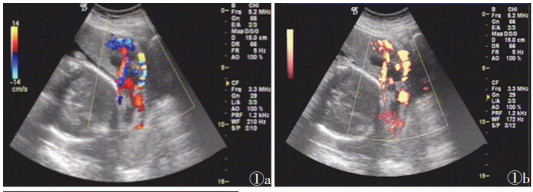

36例胎盘植入中,20例胎盘附着于子宫前壁合并前置胎盘(图 1)。低频超声漏诊3例中,2例胎盘位于子宫后壁并无前置,超声探查胎盘效果不佳,经验不足而漏诊;1例前壁胎盘,无前置,超声图像不典型而漏诊,此孕妇有人工流产史,联合高频超声检查后发现子宫后间隙部分消失子宫肌层变薄,诊断为部分植入。低频超声诊断假阳性3例均为前置胎盘,其中1例联合高频超声检查后确诊为前置胎盘无植入(图 2)。

| 图 1 32岁,孕37周,前置胎盘图 1a,1b CDFI及能量多普勒示靠近植入区域的胎盘及其周边组织血流丰富 |